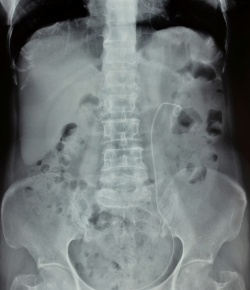

התוויות לחוסר התערבות בנוכחות אבני שופכן

כאשר ניגשים לטפל באבני שופכן, יש לזכור שרובן של האבנים עשוי להיפלט באופן עצמוני עם דרגות נשלטות של אי-נוחות לחולה. היעדר התוויה מוחלטת להתערבות, כגון: זיהום, חסימת שופכן חמורה, כליה בודדת או הפרעה בתפקודי כליות וכאבים בלתי נשלטים, הוא הנחיה למתן הזדמנות לפליטה עצמונית של האבן. גודל האבן ומיקומה לאורך השופכן הם שני הגורמים החשובים ביותר בניבוי פליטה עצמונית והזמן הנדרש להתרחשותה. 71% עד 100% מאבני שופכן בגודל של עד 5 מ"מ עשויות להיפלט עצמונית, אם כי הפליטה יכולה לקחת עד 6 שבועות. שיעור הפליטה של אבנים בגודל שבין 5 מ"מ ל-10 מ"מ יורד ל-25% עד 50% [1] [2] [3] [4]. בשנים האחרונות נכנס לשימוש טיפול תרופתי במטרה לזרז פליטת אבני שופכן בתקופת ההמתנה המבוקרת. תרופות מסוג חוסמי אלפא (Alpha-blockers) כגון Alfuzosin 10 מ"ג, Doxazosin 4 מ"ג, Terazosin 5 מ"ג ו-Tamsulosin 0.4 מ"ג עשויות להעלות את שיעור הפליטה העצמונית של אבני שופכן בכ-20%, ובמקביל לקצר את הזמן עד פליטת האבן ולהקטין את הצורך במשככי כאב אופיואידים [5] [6]. הטיפול התרופתי עלול לגרום לתופעות לוואי ב-3.3% עד 4.2% מהחולים, המתבטאות בירידה בלחץ דם ודפיקות לב [6]. כאבים נשלטים היטב, תפקוד כלייתי שמור והיעדר עדות לאלח דם (Sepsis) הם תנאים הכרחיים להמתנה מבוקרת ו/או לטיפול תרופתי. בתקופת ההמתנה יש לעקוב אחר החולים באמצעות הדמיה תקופתית לקביעת מיקום האבן והערכת דרגת מיימת כליה (Hydronephrosis).

לסיכום, באבני שופכן <10 מ"מ במצב של תסמינים נשלטים, מומלצת המתנה מבוקרת משולבת בטיפול תרופתי. בתקופת ההמתנה, שיכולה להימשך עד 6 שבועות, יש לעקוב אחר התקדמות האבן ומצב מיימת הכליה. התמדה בחסימה, כישלון בהתקדמות האבן, זיהום, פגיעה בתפקוד הכלייתי, או כאבים בלתי נשלטים, הם כולם התוויה להתערבות פעילה.

התוויות להתערבות בנוכחות אבני שופכן

התערבות פעילה מומלצת באבני שופכן מתחת ל-10 מ"מ עם תסמינים בלתי נשלטים, או כישלון של המתנה מבוקרת. באבני שופכן מעל ל-10 מ"מ אין המלצה להמתנה. התמדה בחסימה, כישלון בהתקדמות של האבן, זיהום, פגיעה בתפקוד כלייתי או כאבים בלתי נשלטים הם התוויה להתערבות להוצאת האבן [5]. הסיכוי לפליטה עצמונית עם או בלי טיפול תרופתי באבני שופכן גדולות מ-10 מ"מ הוא קטן ביותר, ולכן מומלץ שלא להמתין לפליטה עצמונית [5]. בחולים שבהם ההמתנה המבוקרת ו/או טיפול תרופתי נכשלו, יש צורך בהרחקת האבן. במקרה כזה ריסוק חוץ-גופי ואורטרוסקופיה הם שני הטיפולים הראשוניים. טיפולים נוספים, הנחשבים כאפשרות משנית, כוללים אורטרוסקופיה מלעורית בכיוון הזרימה (Percutaneous antegrade ureteroscopy), אורטרוליטוטומיה (Ureterolithotomy) לפרוסקופית או ניתוחית פתוחה. הוצאה עיוורת של אבן בעזרת סלסלות שונות, כפי שהיה מקובל לפני יותר מ-25 שנה, אינה מומלצת כיום כאפשרות טיפולית [5].